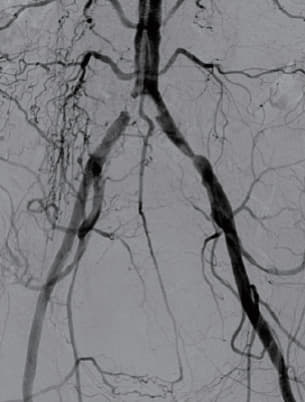

TRI( 左CIAステントグラフト留置 )

本症例は、両側CIA入口部に病変を持つ偏心性石灰化病変であった。止血後の安静困難が予想されたため、TRIによる血管内治療の方針とした。CIA入口部病変は偏心性石灰化が主で、VBX ステントグラフトの良い適応と考えられた。また、大動脈遠位端のプラークは多くなく、プラークシフトの可能性は低いと判断し、TRIのone-site punctureで両側CIAにステントグラフトをシークエンシャルに留置する方針とした。まず狭窄の強い右CIAから治療を開始した。バルーン6.0 × 40 mmで前拡張後、VBX ステントグラフト7.0 × 39 mm(6 Fr)を推奨拡張圧以上で拡張して留置した。血管内超音波(IVUS)により圧着も良好であることを確認し、終了した。次いで左CIAに対して先述のバルーンで前拡張を行い、VBX ステントグラフト7.0 × 59 mm(6 Fr)を推奨拡張以上で拡張し留置した。圧着も良好で終了した。

右CIA VBX ステントグラフト(7.0 × 39 mm)

左CIA VBX ステントグラフト(7.0 × 59 mm)